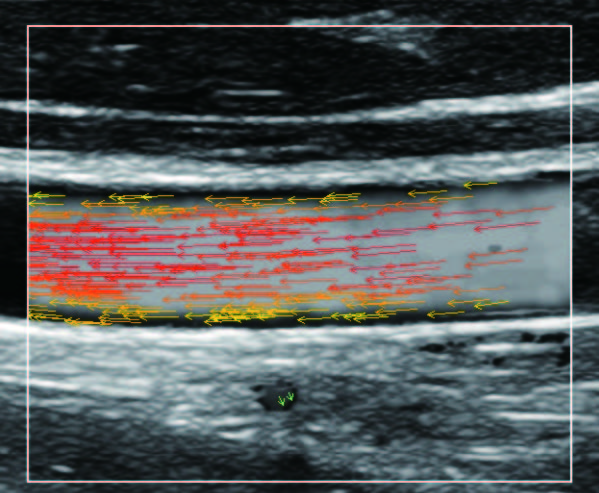

На изображениях, приведенных ниже показаны примеры из клинической практики врачей ультразвуковой диагностики, полученные в процессе апробирования прибора Mindray Resona 7. Приводится наглядные примеры сравнения традиционного режима ЦДК и режима V Flow (Vector Flow).

Изображен ламинарный поток сонной артерии. В режиме ЦДК отсутствует информация о профиле ламинарного потока. Режим V Flow визуализирует не только скоростные характеристики с помощью цветных стрелок, но и предоставляет данные о профиле ламинарного потока (быстрый поток в центре и медленный вблизи стенок сосуда).